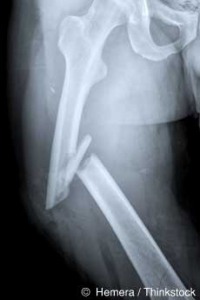

The new study above found that women taking biphosphonates for five years or longer actually showed signs of having weaker femurs,

Taking this drug long-term you have about a three times greater risk of suffering a very unusual fracture either at the socket connecting the femur to the hip, or in the upper femur itself (which is usually the strongest part of the bone).